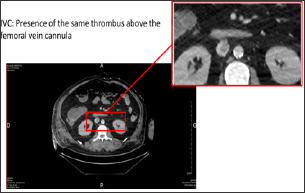

43-year-old patient under noradrenalin was admitted in life-support unit following symptoms of extreme bradycardia associated to 2-minutes low-flow. Initially admitted to the hospital for influenza symptoms with bilateral acute respiratory distress syndrome (ARDS), it appeared rapidly that the patient was indicated for the deployment of an ECMO, which was installed percutaneously between the right femoral vein and jugular vein. At day 12, we observed of a degradation of the respiratory, hemodynamic and renal functions. An increase in the deltaP and the formation of a blood clot indicated a thrombosis of the membrane. The ECMO circuit was completely replaced with a new oxygenation membrane, without changing the cannulas. The patient desaturated very fast during the circuit clamping. Despite the new circuit and oxygenator, a severe refractory hypoxemia persisted conducting to the realization of a thoracic-abdominal-pelvic CT scan (Figure 1), which revealed the presence of a thrombus at the tip of the femoral vein cannula (Figure 2).

Figure 2: Thoracic-abdominal-pelvic CT scan with injection, portal-venous phase, a few imaging above the extremity of the femoral vein cannula.